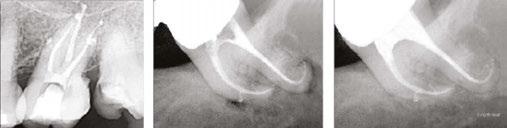

Additionally, the XP-3D Shaper+ can also be used in retreatments. Thanks to its shape, it acts like a corkscrew engaging itself around gutta percha and pulling it out in large pieces (Figure 4). This way, there is no burnishing of the material against the root canal. A speed of 2500 rpm is required in order for the XP-3D Shaper+ to pull out the gutta percha. The XP-3D Shaper+ has been shown to remove gutta percha twice as fast as conventional files.8

Figures 4A-4C: 4A. Non-surgical retreatment protocol using the XP-file family. After creating a well in the gutta percha, solvent is placed and left to react for 2 minutes with gutta percha. The XP-3D Shaper+ is then inserted into the prepared space and rotated at 2500 rpm with gentle strokes at an estimated working length in order to remove the bulk of gutta percha. Once the bulk gutta percha is removed, the working length is established and the Shaper+ reinserted and given 15 strokes to working length at 1000-2500 rpm, followed by 60 seconds with the XP-3D Finisher, ensuring removal of biofilm and gutta-percha tags. The Shaper acts like a corkscrew pulling out the gutta percha. The Finished acts like a scrapper, detaching stubborn gutta-percha tags. 4B. Shaper in retreatment action. Courtesy Dr. Klaus Lauterback, Germany. 4C. Finisher in retreatment action. Courtesy Dr. Rina Campbell, Union City, California